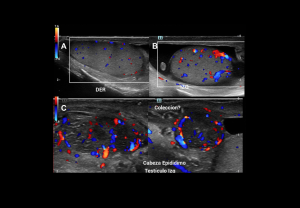

ULTRASOUND ANATOMY OF THE EPIDIDYMIS

Is a 6–7 cm tubular structure along the superolateral border of the testis, divided into three parts:

- Head: converging efferent ductules at the superior pole, extending posteriorly; heterogeneous, isoechoic/slightly hyperechoic to testicular parenchyma; 5–12 mm diameter.

- Body: along the posterior testicular margin; isoechoic to testicular parenchyma; 2–4 mm diameter.

- Tail: at the inferior pole, continues as the ductus deferens; echogenicity similar to testis; 2–5 mm diameter.

Inflammatory Disorders

Epididymo-orchitis

The most common cause of acute testicular pain in adults.

- Clinical findings: tender enlarged testis, scrotal wall thickening, erythema, fever, positive Prehn’s sign, preserved cremasteric reflex.

- Grey-scale: Enlarged heterogeneous epididymis, testicular enlargement with heterogeneous hypoechogenicity, reactive hydrocele.

- Doppler: Diffuse hyperaemia, low-resistance arterial flow (RI: epididymis <0.7, testis <0.5).